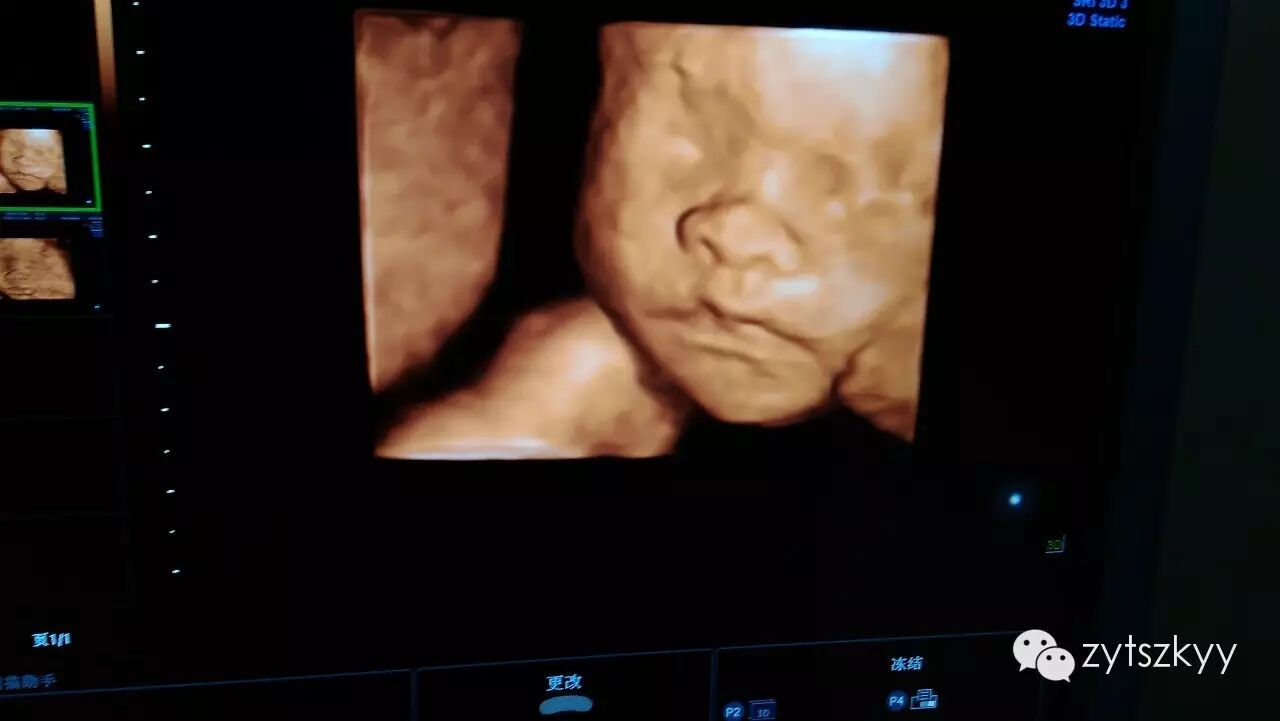

四维彩色超声是目前世界上最先进的彩色超声技术。通过四维重建,能够清楚显示胎儿立体结构宝宝的实时动态活动图像。

原来怀孕不做四维彩超会这么后悔(中医特色专科医院健康科普节目二)-怀孕期

孩子在沉思